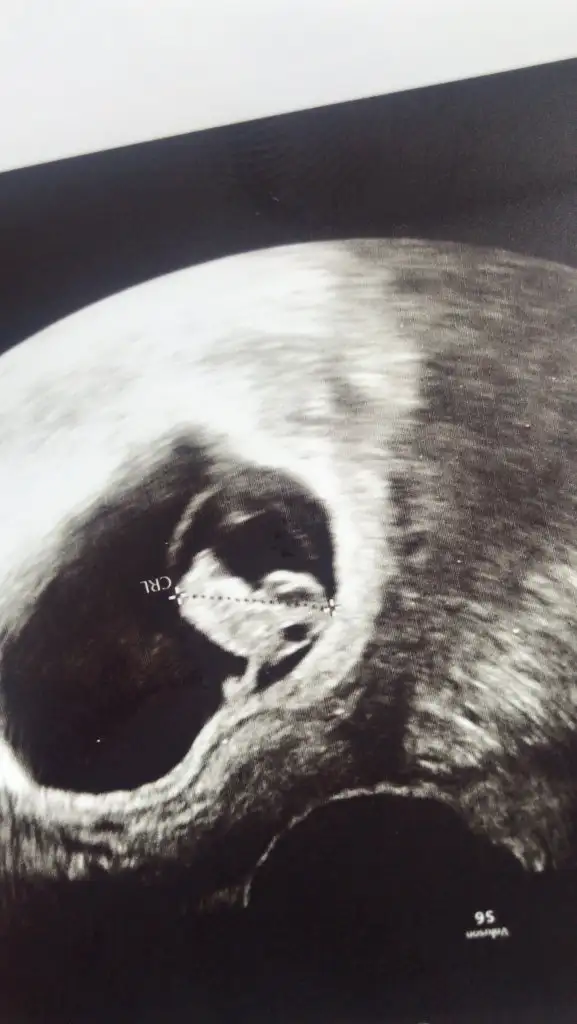

Benimki nedir sence canm?Daha minik annesi11 12 13 haftalar olmalı şimdilik gelişimi erkek gibi ama isteğim haftalar olmalı

Net değil ama kız sanki başka USG varsa paylaşın 11 12 13 haftalar olmalıTahminlerinizi alabilirmiyim??? 12. Haftadan resim

Ayy evet ama heyecanlandımDaha minik annesi11 12 13 haftalar olmalı şimdilik gelişimi erkek gibi ama isteğim haftalar olmalı